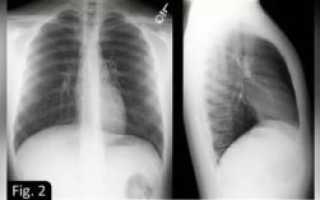

Для выявления причин появления ограниченного затемнения легочного поля, необходимо выполнить снимок в двух направлениях – в прямой проекции и боковой.

По результатам полученных изображений, важно оценить какова локализация очага затемнения.

Если тень на всех снимках находится внутри легочного поля, и сходится размерами с его контурами или имеет меньший объем, логично предположить поражение легкого.

При затемнении, примыкающем широким основанием к диафрагме или органам средостения можно диагностировать внелегочные патологии (жидкостные включения в плевральной полости). Другой критерий оценки ограниченных затемнений – это размер. В этом случае следует рассматривать два возможных варианта:

На рентгеновском снимке ограниченное затемнение легких в двух проекциях